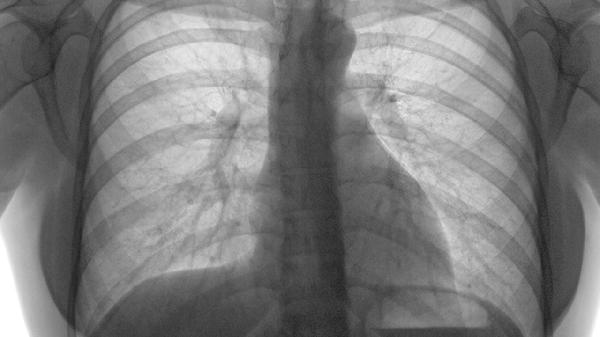

3、AI辅助影像诊断

人工智能系统可识别CT图像中人眼难以察觉的2毫米以下微小结节。